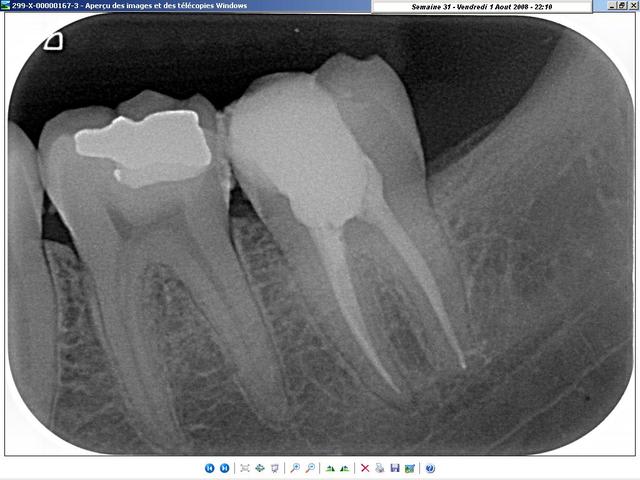

radiologiquement, je ne vois pas trop de différences. A vous de juger.

Les deux cas sont de cette semaine, celui du condenseur, tout frais de cet après-midi; La gutta doit encore être tiède... lol ;-)